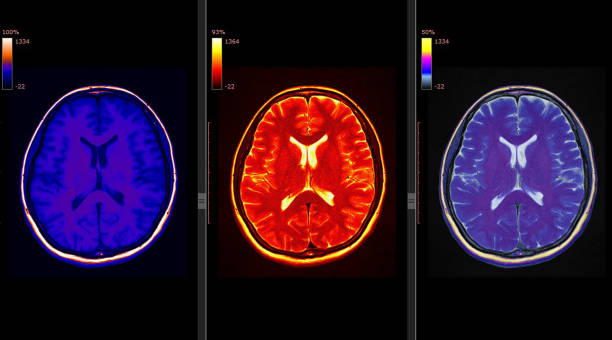

1. 전두엽 손상

뇌경색 후, 이마 부위에 손상이 생기면 하체의 힘이 약해질 수 있습니다. 이로 인해 환자는 걷거나 움직일 때 한 쪽으로 기울거나 반쪽의 마비가 발생할 수 있습니다. 대소변의 장애, 성격 변화, 사고력 저하, 집중력 감소 등과 같은 부작용도 나타날 수 있습니다.

2. 두정엽 손상

두정엽 손상은 실인증과 관련이 있습니다. 환자는 물체를 만져보면 물체를 정확히 인식하지 못하거나, 반대편의 손으로 만졌을 때 자기 몸이 아닌 타인의 몸으로 인식할 수 있습니다.

3. 측두엽 손상

측두엽 손상은 기억력 저하, 청력 감소, 언어 기능 저하 등을 포함합니다. 이 증상은 혈관성 치매로 진행할 수 있으며, 가장 심각한 경우에는 실명에 이를 수도 있습니다.

4. 뇌관 부위 손상

뇌관은 우리 몸의 생체 징후를 담당하는 부위로, 이상이 있는 경우 음식을 적절히 소화하지 못하게 되어 식사에 어려움을 겪을 수 있습니다. 호흡 장애도 발생할 수 있어 인공호흡 장치가 필요할 수 있습니다.